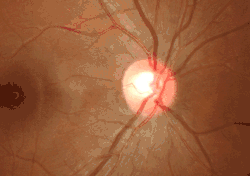

Ophthalmoscopy photograph showing the optic disc as a bright area on the right where blood vessels converge.